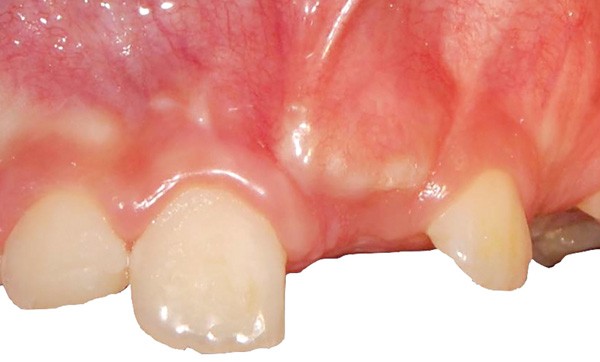

L’un des objectifs de l’orthodontie est d’améliorer l’architecture dento-parodontale et par là même prévenir la survenue de pathologies parodontales sur le long terme. Cependant, certains défauts gingivaux ou pathologies gingivales peuvent déjà être présents avant le traitement orthodontique. Un examen parodontal pré-orthodontique permet de repérer les situations gingivales à risque pour la santé parodontale et indiquer leur correction par des techniques de chirurgie plastique parodontale. D’autres telles que les hyperplasies gingivales ou les récessions gingivales peuvent apparaître au cours des traitements orthodontiques. Un suivi régulier pendant le traitement orthodontique permet de diagnostiquer précocement ces lésions et de les traiter rapidement.

Il semblerait que les mouvements orthodontiques ne représentent pas à eux seuls une cause d’apparition de défauts muco-gingivaux : les biotypes parodontaux et leurs caractéristiques sont tout aussi déterminants. D’où l’importance de savoir évaluer, reconnaître et classer les différents parodontes et défauts muco-gingivaux avant, pendant et après un traitement orthodontique. Le but étant de pouvoir élaborer un plan de traitement parodontal et orthodontique spécifique pour chaque patient en fonction de sa situation parodontale.

Un examen minutieux du parodonte doit être fait avant le début du traitement orthodontique. Il recherche d’éventuels défauts parodontaux et/ou muco-gingivaux ou d’éléments à risque d’en développer lors du traitement orthodontique. Le praticien doit donc se montrer vigilant vis-à-vis de la couleur, la forme et le volume…